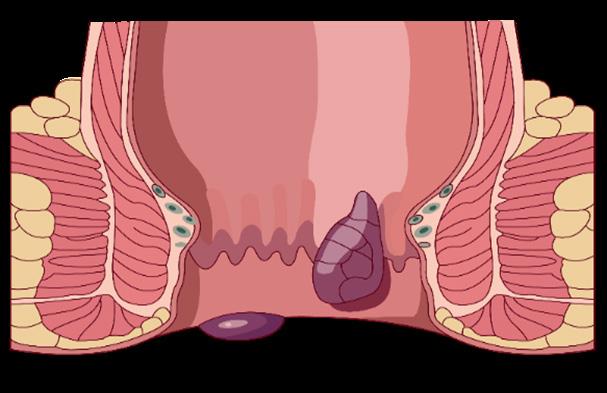

HEMORROIDES

Definición

Son causados por la dilatación de plexos venosos internos (hemorroides interna) o externo (hemorroides externa). Las más frecuentes son las primeras.

Las hemorroides se clasifican como internas, externas o mixtas.

Hemorroides internas

Se desarrolla por encima de la línea dentada, que no está inervada por nervios cutáneos; la distensión no causa dolor.

El prolapso de las hemorroides internas con posible encarcelamiento y estrangulamiento, puede causar dolor al desencadenar un espasmo del complejo del esfínter anal. → posible isquemia y necrosis de hemorroides internas → empeoramiento del espasmo del complejo del esfínter anal → posible trombosis hemorroidal externa → dolor cutáneo

Las hemorroides internas sangrantes y / o prolapsadas irritan la piel perianal sensible → picazón perianal

Hemorroides externas

Se desarrollan por debajo de la línea dentada, que está inervada por nervios cutáneos; distensión de esta piel inervada debido a un coágulo o edema produce un dolor intenso

Cuadros agudos con trombosis generan dolor, con una duración de 7-14 días

En caso de las hemorroides internas (clasificación de Goligher) (ESSALUD 2004)

Grado I: las hemorroides no se prolapsan, son reversibles, se ubican por encima de la línea dentada y pueden visualizarse en la anoscopia

Grado II: prolapso de hemorroides con esfuerzo, pero se reducen espontáneamente

Grado III: prolapso de hemorroides con esfuerzo y solo se pueden reducir manualmente

Grado IV: prolapso irreducible